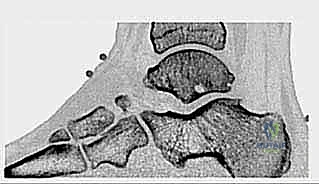

* الأشعة السينية (X-rays): بوضعيات خاصة (Lateral view) لرؤية العظم الزائد (Os Trigonum) والنتوءات العظمية وتضيق المسافات المفصلية.

* الأشعة المقطعية (CT Scan): تُستخدم في حالات معينة لعمل خريطة ثلاثية الأبعاد للكسور القديمة أو التكلسات العظمية المعقدة قبل الجراحة.

1. متلازمة انحشار الكاحل الخلفي والعظم الزائد (Os Trigonum Syndrome)

تُعد هذه المتلازمة من أكثر الأسباب شيوعاً، خاصة لدى الرياضيين (لاعبي كرة القدم) والراقصين (الباليه). العظم الزائد (Os Trigonum) هو عظم إضافي خلقي صغير يقع خلف عظم الكاحل (Talus). في الحالات الطبيعية، قد لا يسبب ألماً، ولكن مع الثني القسري المتكرر للقدم نحو الأسفل (Plantar Flexion)، ينحشر هذا العظم بين عظم الظنبوب وعظم العقب، مما يؤدي إلى التهاب شديد وتمزق في الأنسجة المحيطة به.